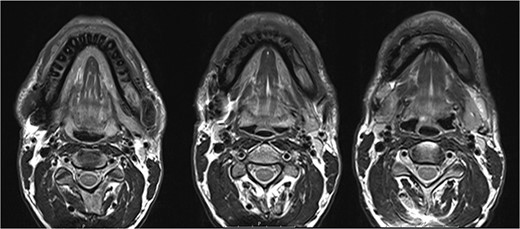

The MRI performed three months after the last pamidronate infusion revealed a significant reduction of enhancement in the mandible with some patchy hypointense areas remaining (Fig. 5).

Magnetic resonance imaging (MRI) 3 months after bisphosphonate therapy. T2 weighting shows the significant reduction of inflammatory activity within the mandible after bisphosphonate treatment.